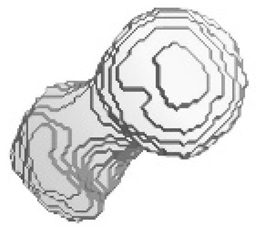

| Ground truth and predicted results of the left femur under dataset category F-II | ||||||

| Front | Left | Rear | Right | Top | Bottom | |

| Prediction |  |  |  |  |  |  |

| SAM | 0.155 | 0.165 | 0.144 | 0.135 | 0.187 | 0.236 |

| SSIM | 0.677 | 0.658 | 0.712 | 0.714 | 0.701 | 0.689 |